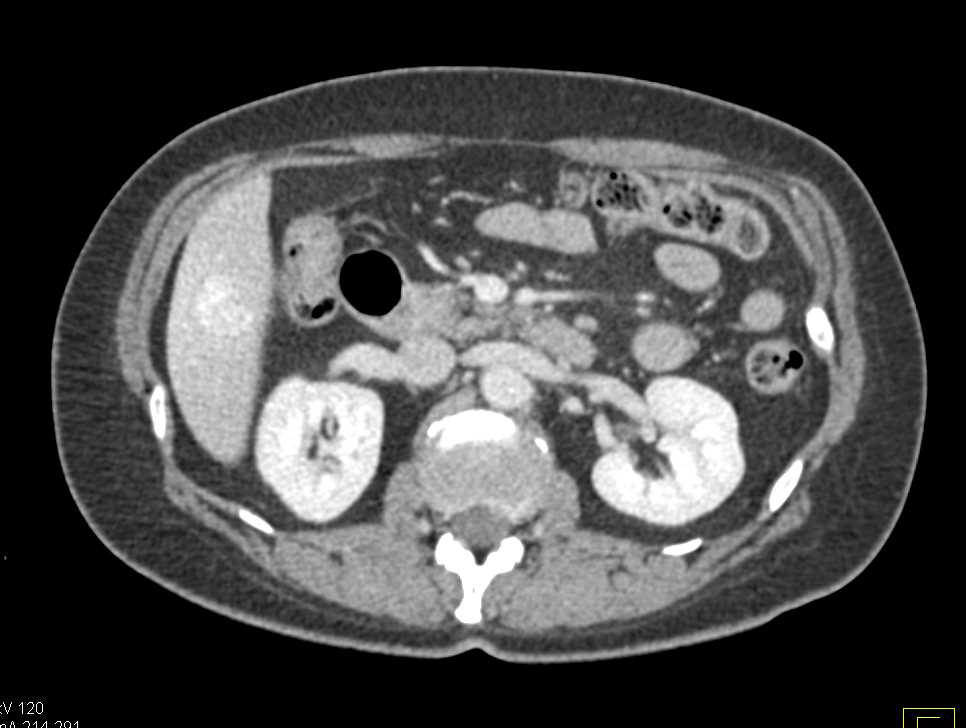

Ovarian Carcinomatosis